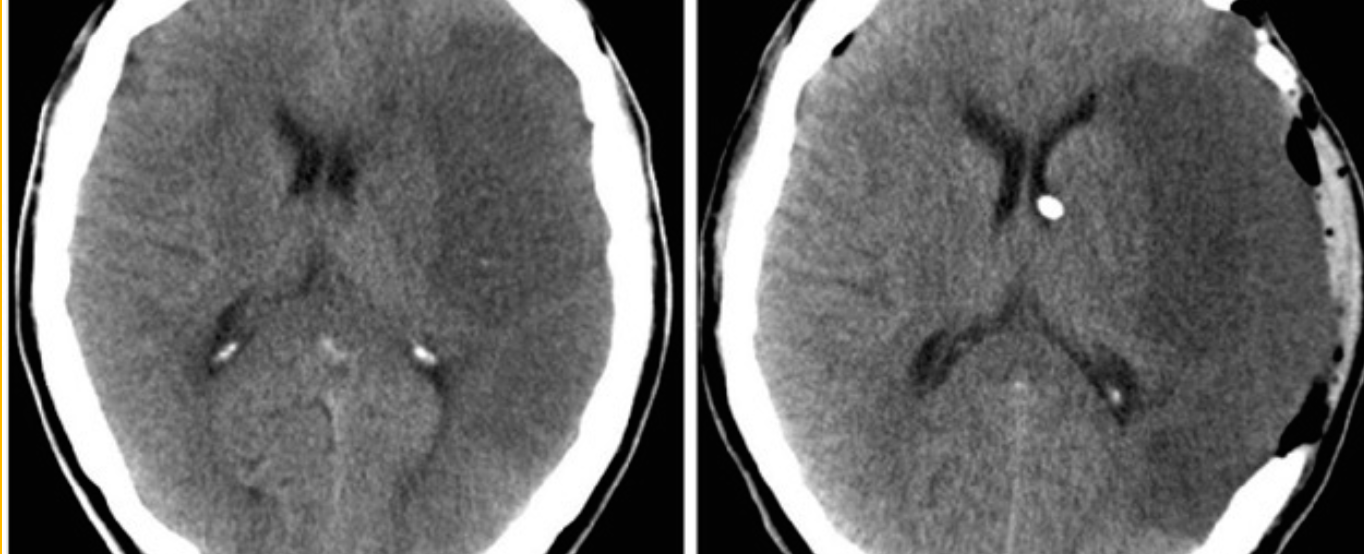

Axial CT scan obtained in a 57-year-old man who presented with left hemiplegia and obtundation.

Axial CT scan obtained in a 57-year-old man who presented with left hemiplegia and obtundation.

Name the site of the lesion?

---basal ganglia---

What is commonest cause of this lesion?

---hypertension---